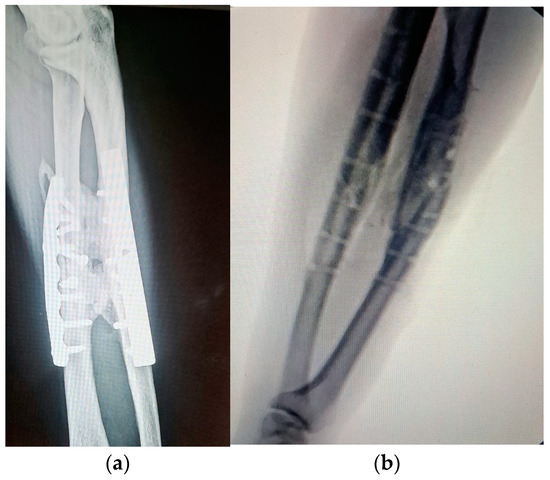

Treatment of Recalcitrant Isolated Congenital Fibular Pseudarthrosis: Fibular Segment Transfer and Tibiofibular Synostosis with Unilateral External Fixator

Isolated congenital pseudarthrosis of the fibula is a rare entity with a limited number of cases reported in the literature. Treatment is challenging because of recalcitrant nonunion and because no consensus about the best treatment plan exists. We report a case of isolated [...] Read more.

Isolated congenital pseudarthrosis of the fibula is a rare entity with a limited number of cases reported in the literature. Treatment is challenging because of recalcitrant nonunion and because no consensus about the best treatment plan exists. We report a case of isolated congenital fibular pseudarthrosis with valgus deformity of the ankle. The patient had a history of two failed operations. We used a novel surgical plan that combined tibiofibular synostosis with fibular segment transfer through a unilateral external fixator. The patient showed good early results with fibular union. We advocate the combination of tibiofibular synostosis and fibular segment transfer to restore the integrity and stability of the ankle in recalcitrant isolated congenital fibular pseudarthrosis cases with a history of failed surgery. Full article